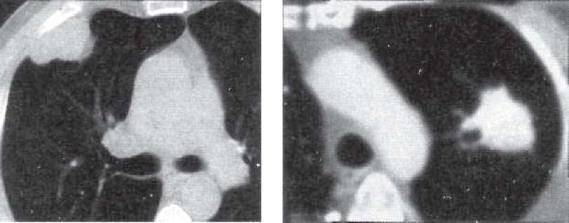

Периферическая карцинома легких: Роль КТ в диагностике